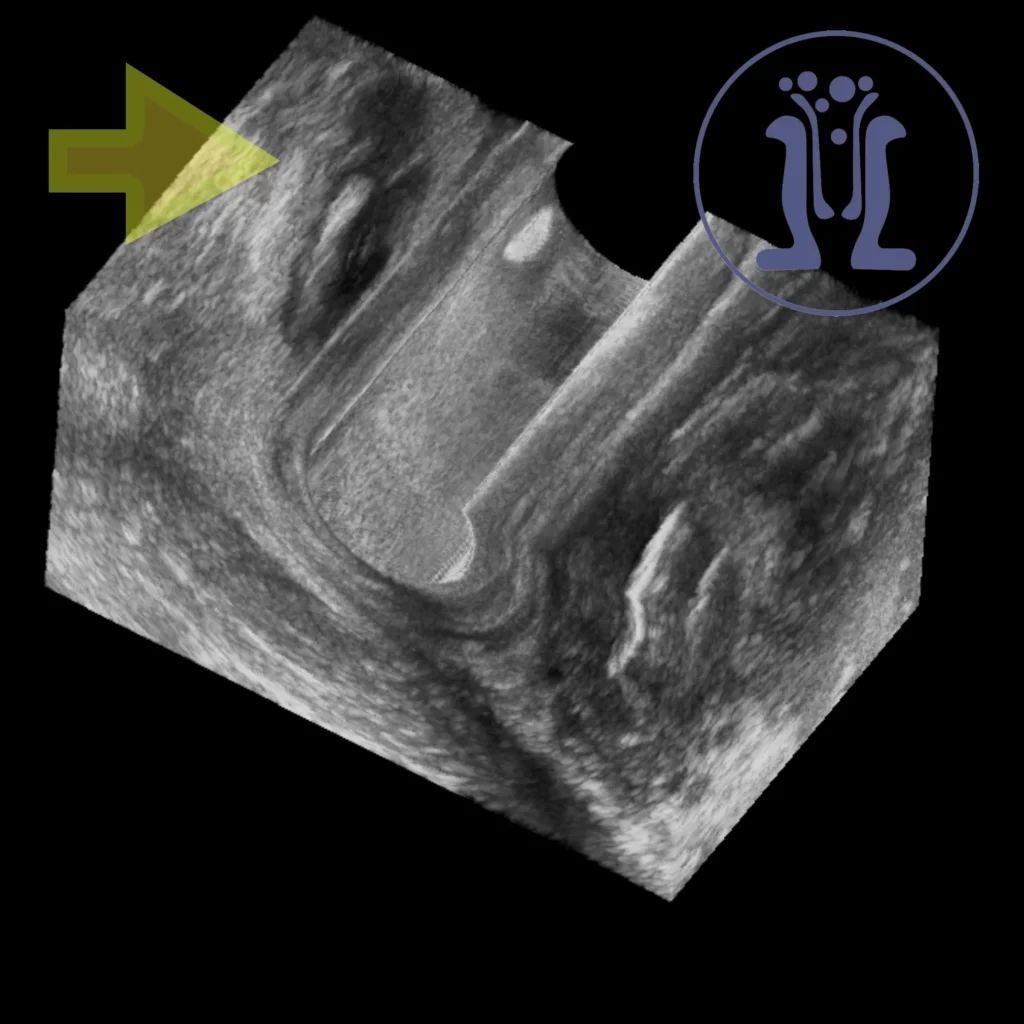

Το ενδοπρωκτικό υπερηχογράφημα δείχνει μία κύστη στο οπίσθιο άνω τεταρτημόριο του πρωκτικού σωλήνα με χαρακτήρες οπισθοορθικής κύστης. Η οπίσθοορθική κύστη είναι μία κύστη που αναπτύσσεται πίσω από το ορθού και πιθανότατα προκαλείται από παραμονή και περαιτέρω ανάπτυξη εμβρυικού υπολείμματος.